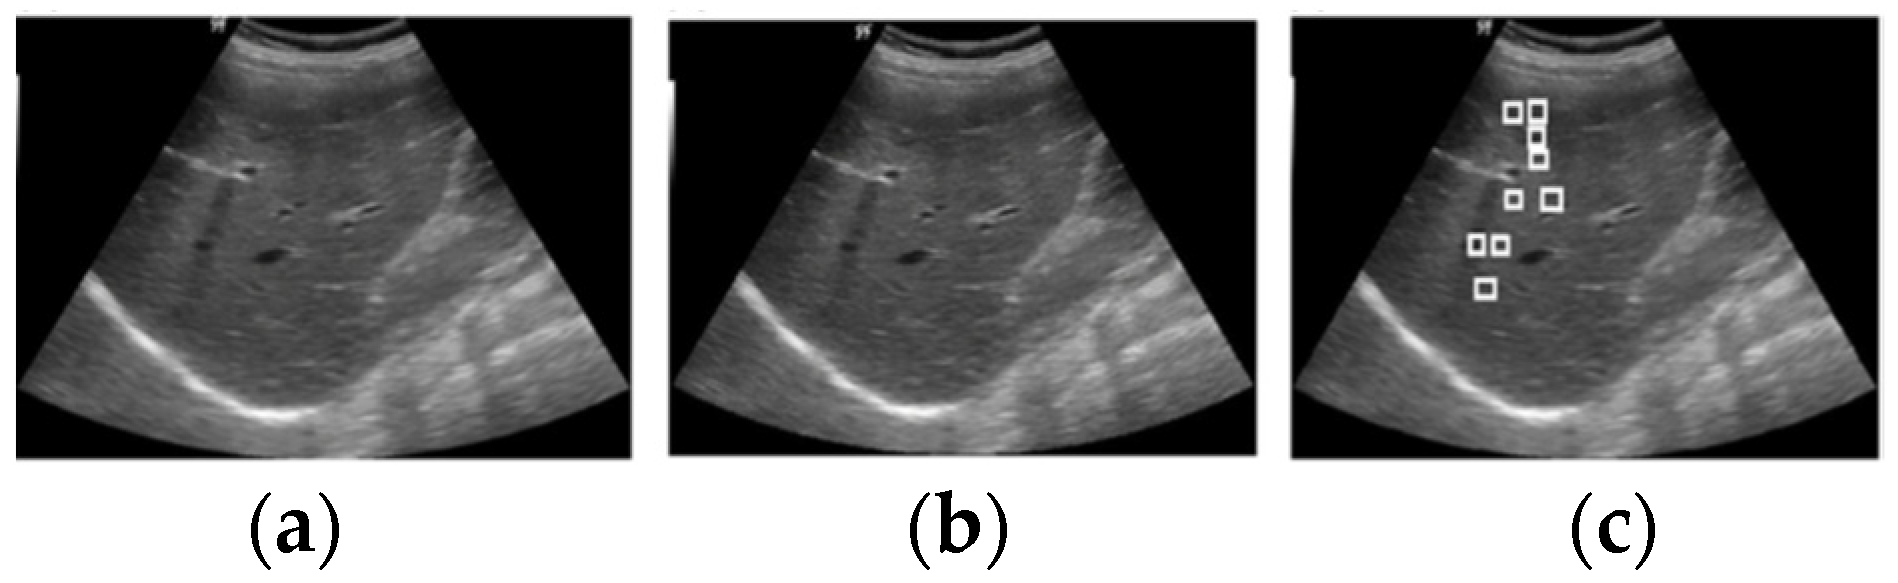

3.1. Image Acquisition